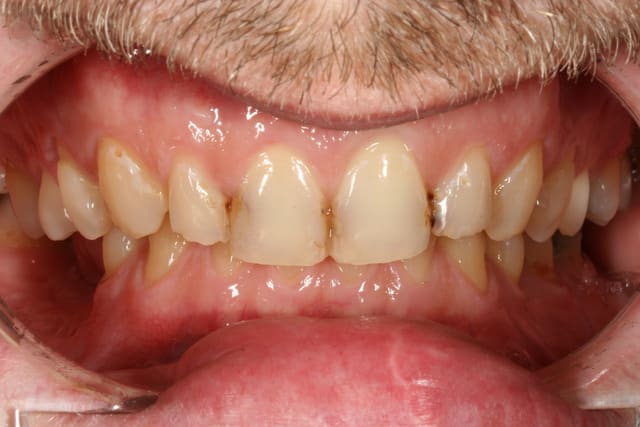

pour l'occlusion, voilà les photos, il y a effectivement une classe II, plus marquée à droite qu'à gauche

il y a l'absence de la 36 depuis quasiment l'enfance, l'occlusion est calée comme ça depuis plus de 30 ans et ça ne bouge pas

il n'y a pas (ou peu) de supraclusion (overbite je crois que c'est ça)

il n'y a aucun problème musculaire ou articulaire

quand on a des supraclusions comme ces deux patients en photo, je dis pas, mais on me semble très loin de ça pour ma patiente ici

Img 9257 lz7zgv - Eugenol

Img 9231 savtqx - Eugenol